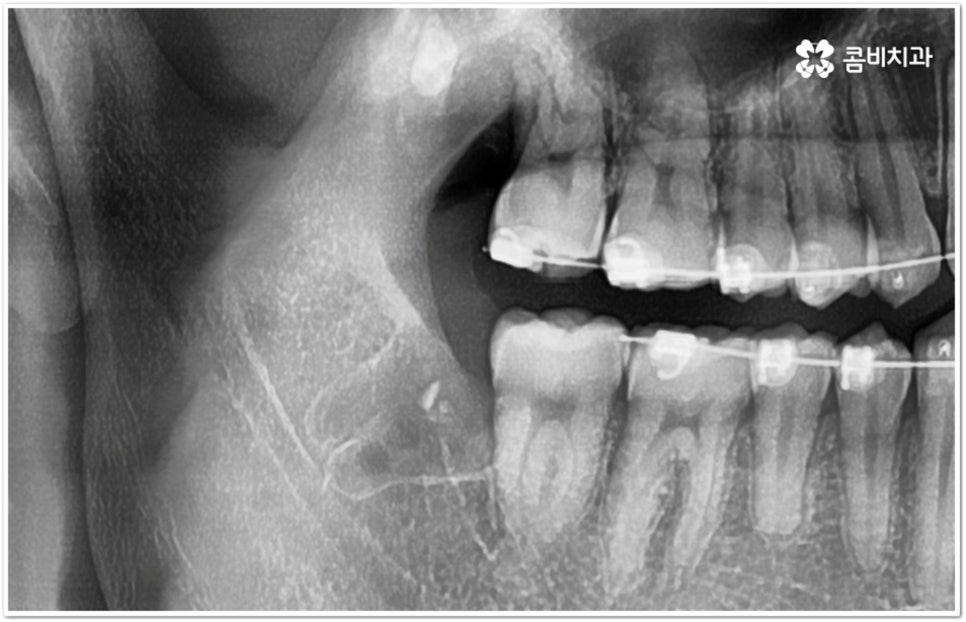

만약 똑바로 자라나고 관리가 용이하며 마주보는 대합치 역시 정상적으로 맹출되었다면 사랑니를 꼭 발치할 필요는 없을 거예요. 그러나 보통 사랑니는 사람의 치아 중에 가장 마지막에 나오는 치아라서 이미 구강 내 공간이 비좁은 상태이기 때문에 비스듬하게 자리를 잡고 일부분만 맹출이 되는 경우가 많이 있어요. 보통 머리가 앞쪽으로 기울어진 근심위로 자리잡는 케이스가 가장 많으며 그 밖에도 치아 머리가 뒤쪽으로 기울어져 있거나 혀쪽, 볼쪽으로 누운 케이스, 아예 옆으로 완전히 누운 케이스 등도 발견되고 있는데요.

잇몸에 반쯤 덮힌 채로 삐뚤게 나온 사랑니는 칫솔질을 제대로 하기 어렵고 위생 관리가 잘 되지 않아 주변 잇몸에 염증이 생기기 쉬우며 어금니까지 충치가 번질 위험이 높아지게 되어 구강 건강 관리 및 예방 차원에서 발치 처치를 해주실 필요가 있어요. 발치 난이도는 사랑니의 경사 각도와 방향 및 치아 뿌리의 길이와 개수, 사랑니 뒤쪽 턱 뼈의 각도 및 형태, 하치조 신경 또는 상악동까지의 거리 등에 따라서 달라질 수 있습니다.

이때 아래사랑니발치 의 경우 아래턱 부근을 지나가는 큰 신경인 하치조 신경을 건드리지 않고 조심스럽게 사랑니만 제거해야 하기 때문에 3D-CT 등 정밀 검진 기계를 통해 사랑니의 매복 위치, 깊이, 각도 등의 상태와 신경까지의 거리 등을 먼저 꼼꼼하게 파악한 후에 발치를 해 줄 필요가 있는데요. 만약 완전히 매복되어 있다면 사랑니 주변에 함치성 낭종이 발생할 수도 있는데 이로 인해 주변 치조골이 파괴되고 어금니 쪽으로 병변이 확산되면 결국 치아를 상실하게 되거나 턱뼈가 약해져서 작은 충격에도 부러지는 현상이 발생할 가능성도 있으므로 될 수 있는대로 치료 시기를 놓치지 않는 것이 중요한 포인트라고 할 수 있어요.

아래사랑니발치 와 다르게 윗 사랑니 발치 시에는 상악동까지의 거리가 너무 짧을 경우 천공 및 감염의 위험이 있으니 이에 대해서 3D CT 를 통해 꼼꼼하게 확인하고 환자분들의 상황에 맞는 치료를 진행할 필요가 있어요. 예를 들어 사랑니로 인한 문제가 크지 않은 경우 그대로 두고 지켜볼 수도 있고 다른 치료를 하는 중에, 즉 교정이나 임플란트 등을 진행하는 과정에서 발치가 꼭 필요한 경우라면 상악동 거상술, 뼈이식 등의 치료를 선행하여 무리하지 않게 뽑아주는 것이 좋을 거예요.